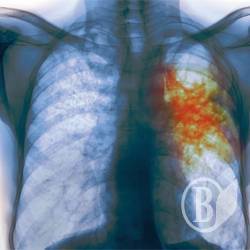

Одна із виховательок чернігівського дитсадка №22 виявилася хворою на відкриту форму туберкульозу.

«А у травні вона виявилася хворою відкритою формою туберкульозу, хоча ця стадія триває від 6 до 10 місяців. Лікарі ж на зборах запевняли, що вона тільки-но захворіла» - пише Вікторія Пискун.

Усім вихованцям дитсадка призначили зробити проби Манту, тим, хто тісно контактував з хворою вихователькою – зроблять флоорографію.